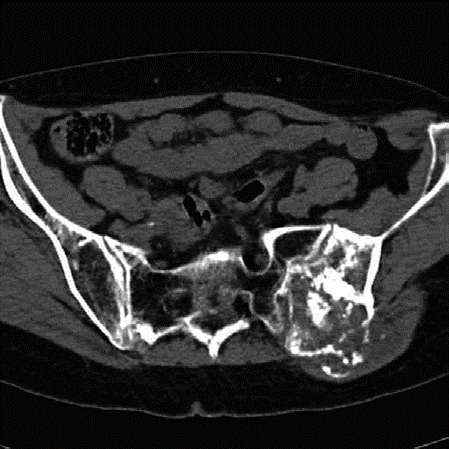

Lower limb Trauma Structured oral examination question 7 A 78-year-old woman fell out of her bed and sus- tai…

Lower limb Trauma Structured oral examination question 6 A 50-year-old woman, front-seat passenger, was invol…

Lower limb Trauma Structured oral examination question 1 A 35-year-old motorcyclist came off his bike yester-…